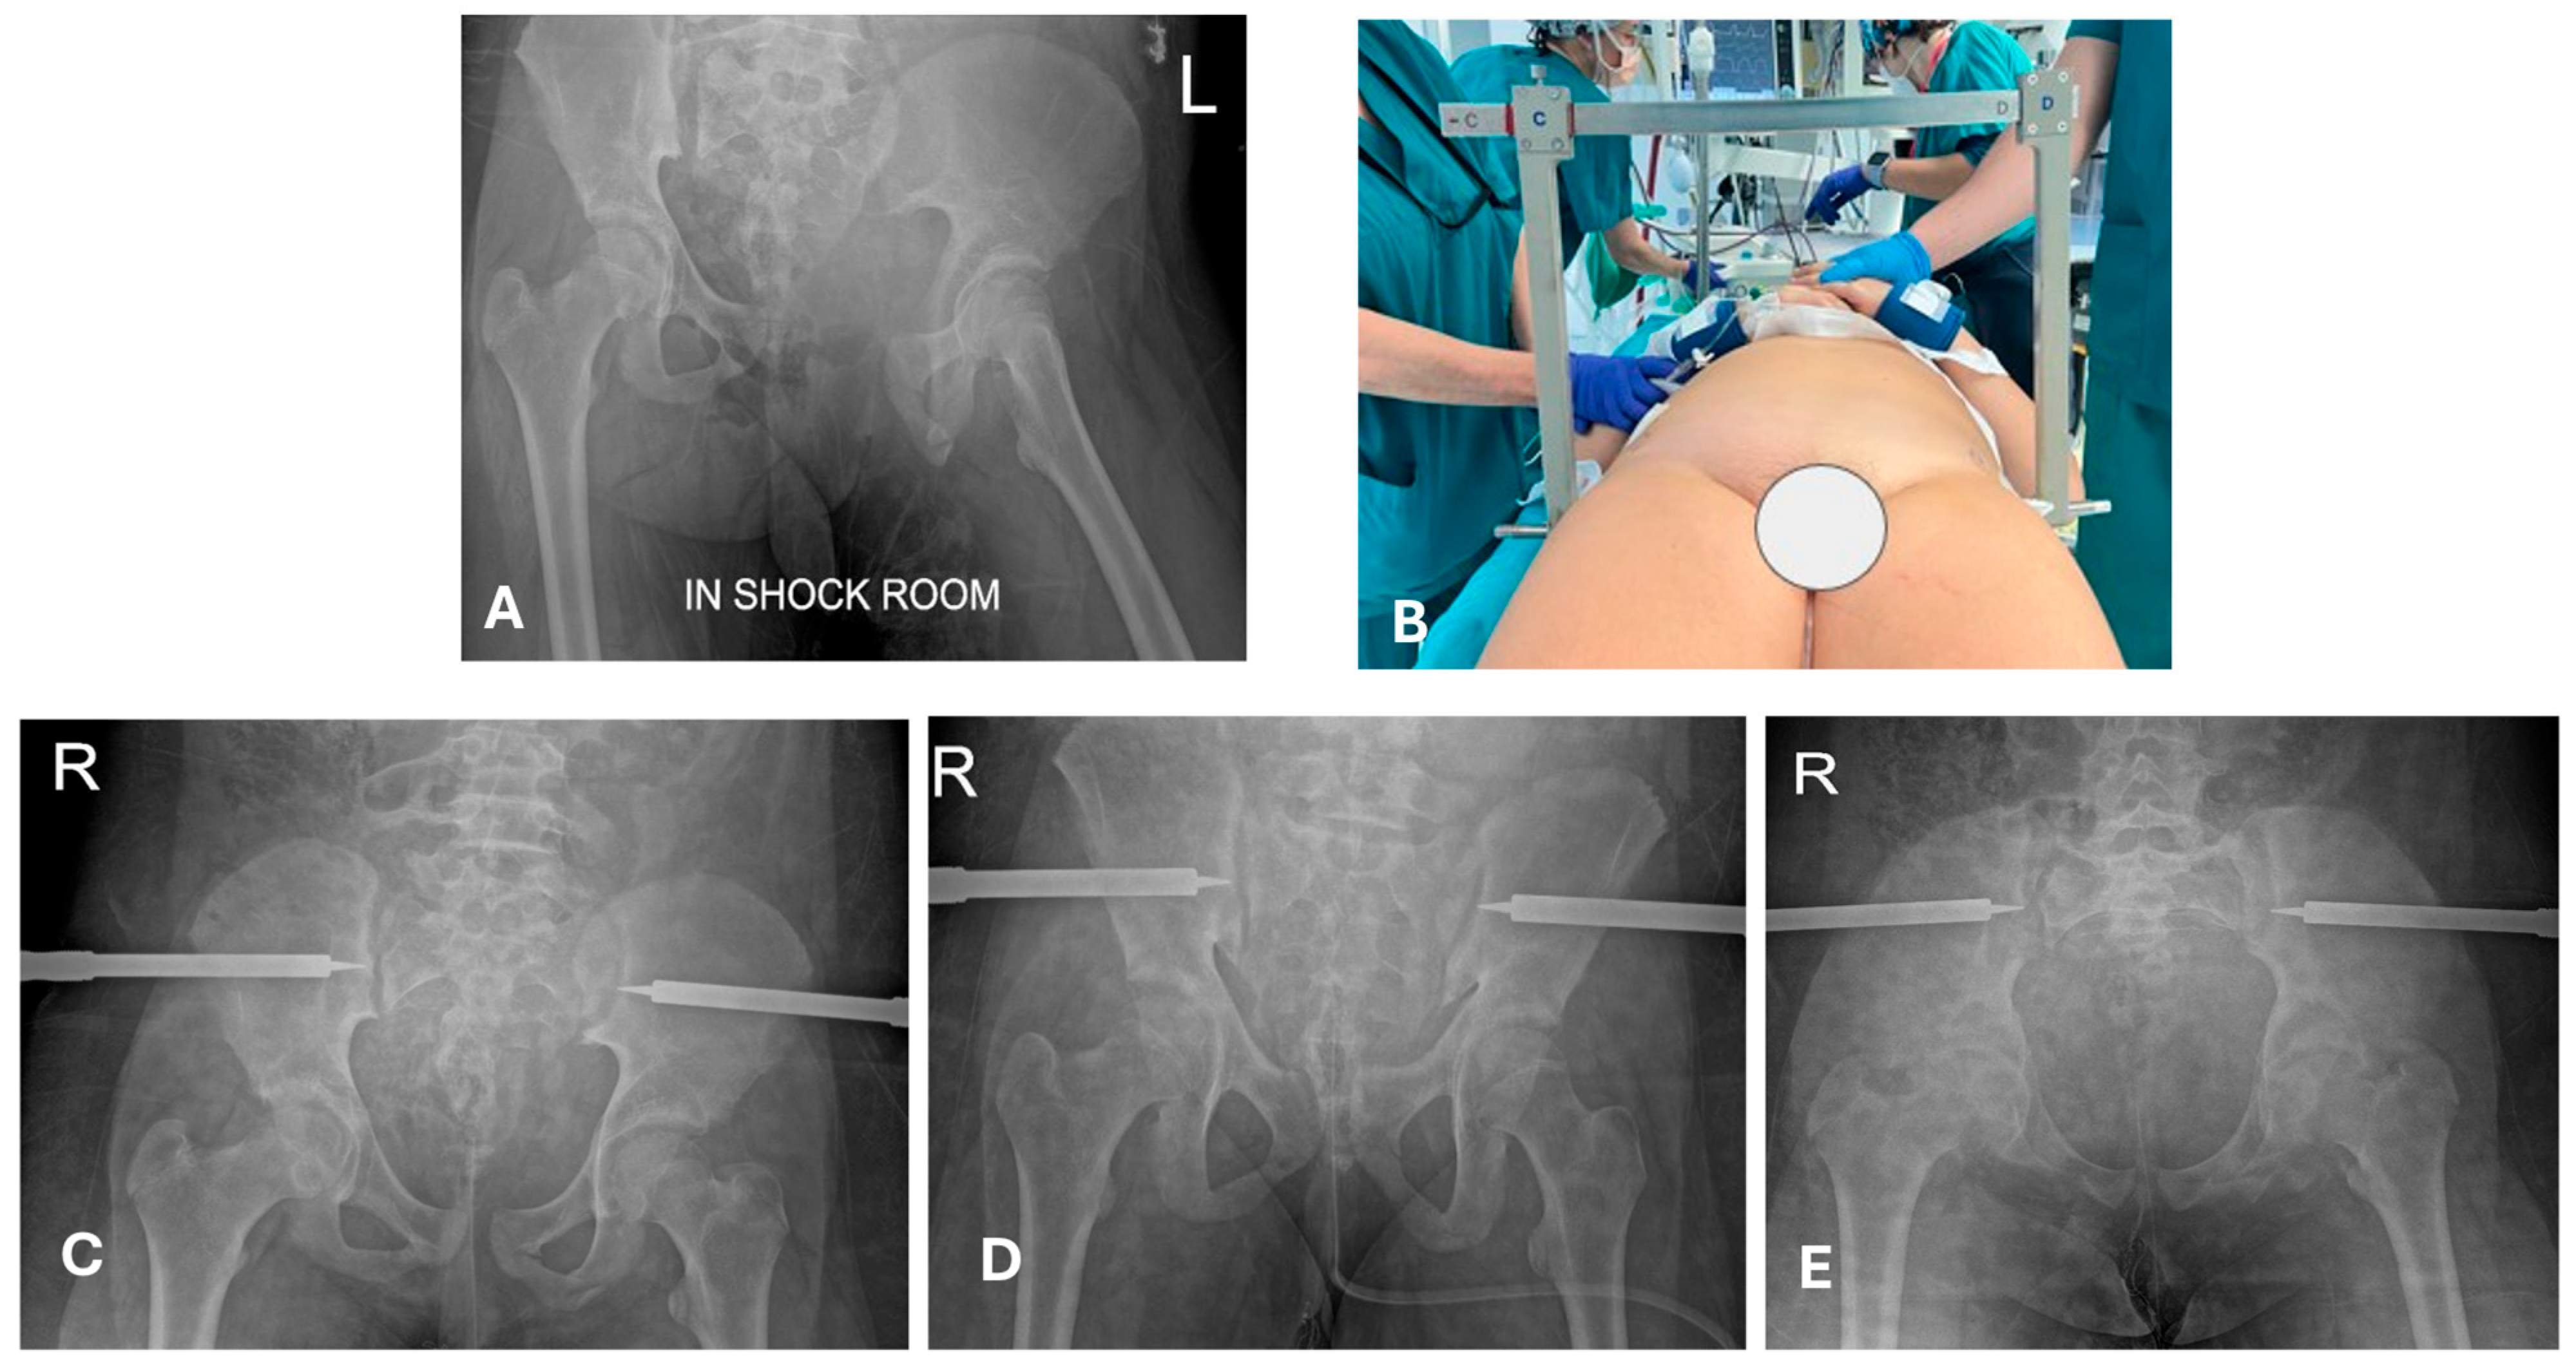

4.2. Is a Temporary Damage Control Surgery (DCO) Indicated?